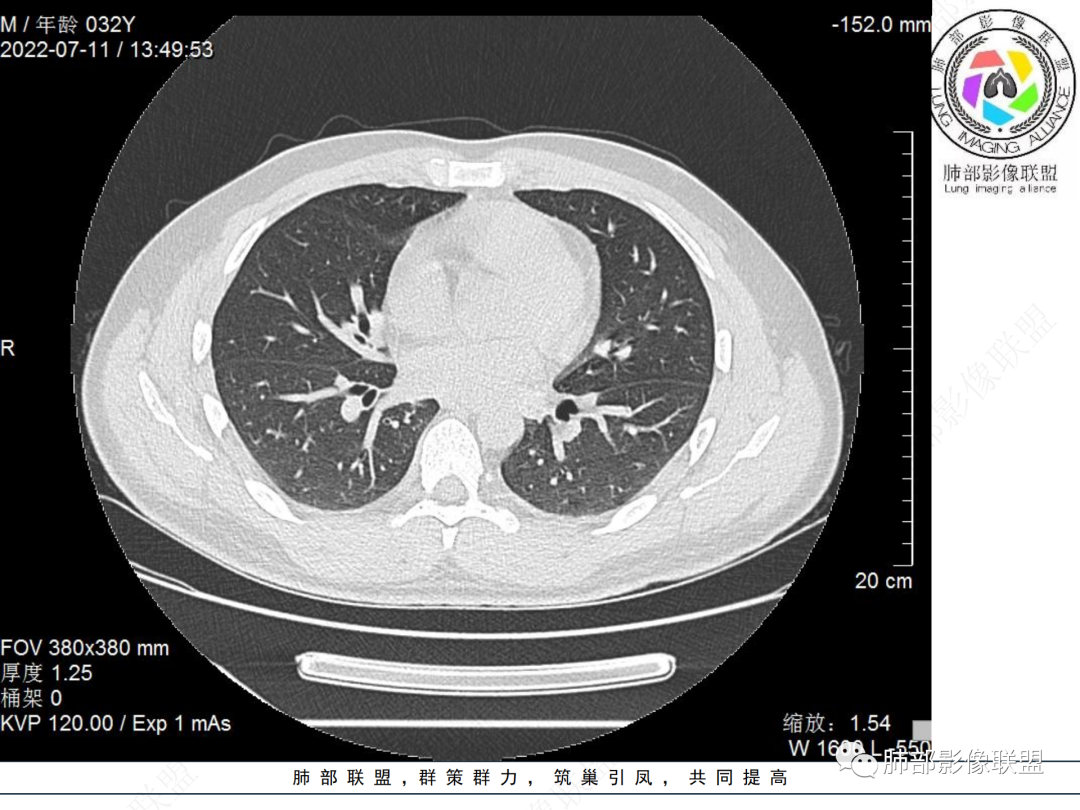

左肺下叶后基底段开口处结节,边缘光滑清楚,没有增强扫描,年轻男性患者痰血三天,考虑1.良性病变:腺瘤、错构瘤、平滑肌瘤

2.恶性:类癌、粘液表皮样癌。

左肺下叶外后基底段气管内见结节状影,边缘部分清晰。考虑错构瘤,待排恶性病变。

左肺下叶气管内外占位病变,咯血病史,考虑类癌,粘表待排。

青年男性,左肺下叶后基底段支气管开口软组织结节,边缘光整,气管镜提示质软,易出血,考虑类癌

左肺下叶后基底段开口处结节,边缘光滑清楚,年轻患者考虑鳞癌或腺样囊腺癌

左肺下叶气道腔内占位,远端无花花草草,疾病谱:鳞,类癌,粘表,腺样囊腺癌,小,无增强,不好判断,临床咯血,选类癌。

大支气管腔内结节,考虑类癌

左肺下叶后基底段开口处结节影,边缘光滑,患者年龄较小,首选类癌

男性,咳血左肺下叶支气管腔内结节影,没有阻塞性炎症,考虑类癌,鳞癌

年轻男性,支气管内结节,首先类癌

左肺下叶后基底段开口处腔内见壁结节,花生米样,宽基底,补充增强及矢状位重建,确定我无向壁外突破浸润生长,另见强化的特点,临床触之易出血,类Ca可能性大。

年轻男性,支气管腔内占位,边缘尚平整,年轻人,首先类癌,鉴别错构

年轻男性,咳血,左肺下叶后基底段支气管腔内结节,边缘光滑,首先考虑青年三件套,类癌大于粘液表皮样癌,支气管镜质软,触之易出血,鉴别血管瘤,平滑肌瘤

左肺下叶后基底段开口部结节,密度较均匀一致,边缘较光整,目测密度偏低,支气管镜示:质软、触之易出血,考虑恶性,类癌。

支气管腔内结节,有蒂与支气管壁连接,考虑良性病变可能性大,支气管错构瘤 血管瘤一类的

左肺下叶后基底段支气管腔内结节,有蒂,容易出血,先考虑良性病变,肉芽组织型血管瘤,与类癌鉴别。

青年男性,左肺下叶后基底段支气管开口软组织结节,边缘光整,气管镜提示质软,易出血,考虑恶性类癌

左肺下叶后基底段开口处结节影,边缘光整,年轻患者,伴咯血,考虑鳞癌,类癌不能排除